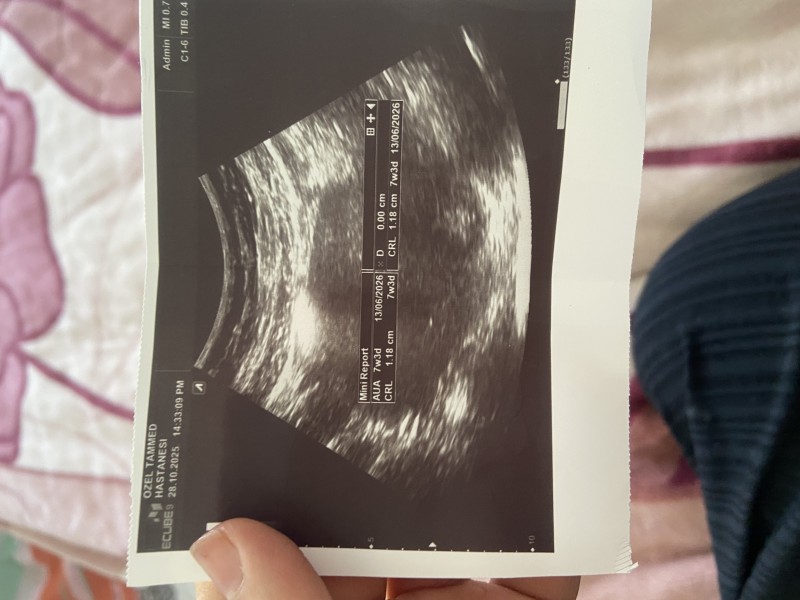

Kızlar bazıları bebeğin cinsiyetini 6. Haftadan sonra tahmin edebiliyorlar kesenin şekline yönüne vs bende 7 haftalığım merak ettim halk arasında ultrasona göre cinsiyet tahmini yapar mısınız

ne kese belli ne şekli 😂 o ölçümleri doktor niye ortada vermiş ki kenarda olur

belli değil ki işte. doktor da ölçümleri ortaya koymuş. kenarda olsa belki belli olurdu

O ortadaki çizgi olmasaydı tahmin yürütürduk ortada bebiş Yok  çizgi yüzünden.

Canım kese belli olmuyır ki hiç. Benim oğlumda kese fasulye gibiydi şimdi bidaha hamileyim yuvarlak bakalım bilmiyorum cinsiyeti öğrenemedim. Fasulye olunca erkek yuvarlak olunca kız derler ama doğruluk payı yok yani değişik olabiliyor

İkinci gebeliğim ilk bebeğim erkek ve bütün ultrason resimlerini sakladım az önce baktım hepsinde kese fasulye şeklindeydi bunda da yuvarlak denilince kız merakı sardı 😁